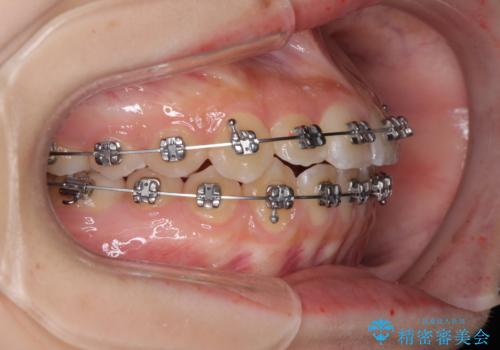

前歯のクロスバイト メタル装置での矯正治療

- メタルブラケット

- 前歯のクロスバイトを気にして来院された患者様です。

前歯の叢生を解消するスペースを獲得するために上顎左右の親知らずを抜歯し、メタルブラケットにて矯正治療を行うこととしました。